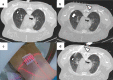

Image-guided percutaneous lung ablation has proven to be a valid treatment alternative in patients with early-stage non-small cell lung carcinoma or oligometastatic lung disease. Available ablative modalities include radiofrequency ablation, microwave ablation, and cryoablation. Currently, there are no sufficiently representative studies to determine significant differences between the results of these techniques. However, a common feature among them is their excellent tolerance with very few complications. For optimal treatment, radiologists must carefully select the patients to be treated, perform a refined ablative technique, and have a detailed knowledge of the radiological features following lung ablation. Although no randomized studies comparing image-guided percutaneous lung ablation with surgery or stereotactic radiation therapy are available, the current literature demonstrates equivalent survival rates. This review will discuss image-guided percutaneous lung ablation features, including available modalities, approved indications, possible complications, published results, and future applications.